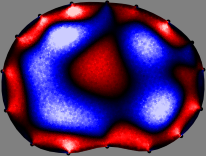

Refer to caption

Figure 2: Fidelity-embedded regularization method. (Left bottom) Correlations between four different column vectors (𝐒ksubscript𝐒𝑘{\bf S}_{k}) and all the remaining column vectors (𝐒subscript𝐒{\bf S}_{\ell}) are visualized. (Right bottom) Performances of the proposed fidelity-embedded regularization method for λ=𝜆\lambda=\infty are shown by numerical simulations.

To explain the FER method, we closely examine the correlations among column vectors of the sensitivity matrix 𝕊𝕊\mathbb{S}, described in Fig. 2. The correlation between 𝐒ksubscript𝐒𝑘{\bf S}_{k} and 𝐒subscript𝐒{\bf S}_{\ell} can be expressed as

for i=1,,16𝑖116i=1,\cdots,16[23]. This shows that the column vector 𝐒ksubscript𝐒𝑘{\bf S}_{k} is like an EEG (electroencephalography) data induced by dipole sources with directions uj,j=1,,16formulae-sequencesubscript𝑢𝑗𝑗116\nabla u_{j},j=1,\cdots,16 at locations ΔksubscriptΔ𝑘\Delta_{k}. Given that two dipole sources at distant locations produce mutually independent data, the correlation between 𝐒ksubscript𝐒𝑘\mathbf{S}_{k} and 𝐒subscript𝐒\mathbf{S}_{\ell} decreases with the distance between ΔksubscriptΔ𝑘\Delta_{k} and ΔsubscriptΔ\Delta_{\ell}. Fig. 2 shows a few images of the correlation 𝐒k,𝐒(|𝐒k||𝐒|)1subscript𝐒𝑘subscript𝐒superscriptsubscript𝐒𝑘subscript𝐒1\left\langle\mathbf{S}_{k},\mathbf{S}_{\ell}\right\rangle(|\mathbf{S}_{k}||\mathbf{S}_{\ell}|)^{-1} as a function of \ell for four different positions ΔksubscriptΔ𝑘\Delta_{k}. The correlation decreases rapidly as the distance increases. In the green regions where the correlation is almost zero, 𝐒subscript𝐒{\bf S}_{\ell} is nearly orthogonal to 𝐒ksubscript𝐒𝑘{\bf S}_{k}.

Fig. 2 shows that if ΔksubscriptΔ𝑘\Delta_{k} and ΔsubscriptΔ\Delta_{\ell} are far from each other, the corresponding columns of the sensitivity matrix are nearly orthogonal. This somewhat orthogonal structure of the sensitivity matrix motivates an algebraic formula that directly computes the local ensemble average of conductivity changes at each point using the inner product between changes in the data and a scaled sensitivity vector at that point: